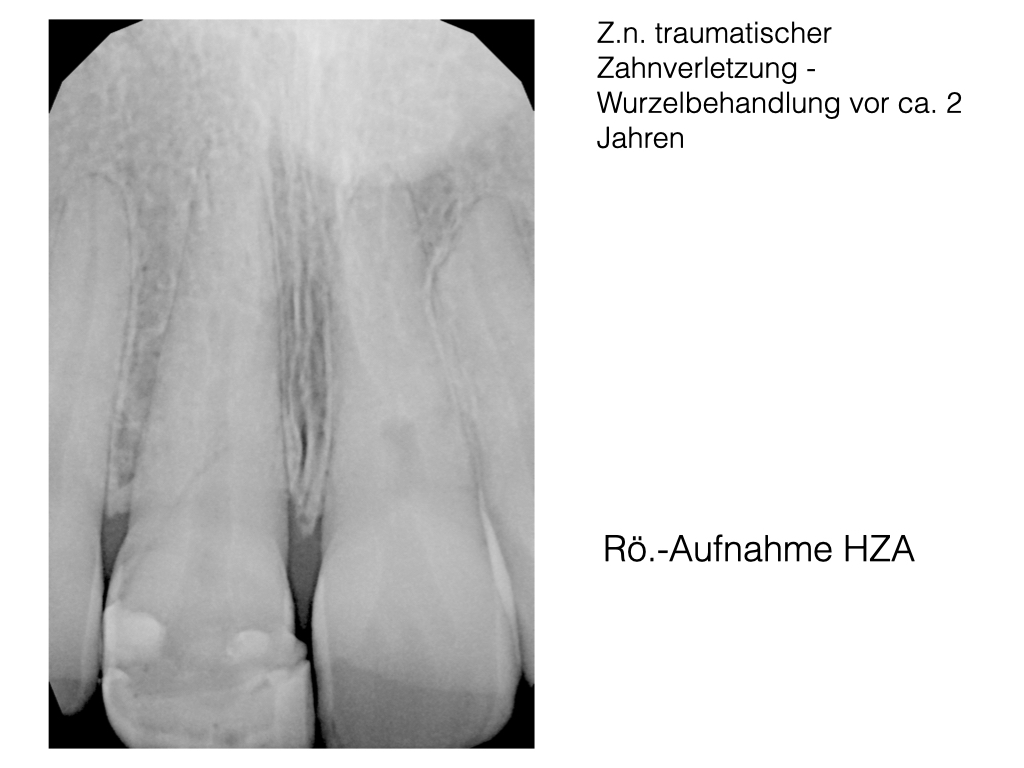

Schmerzfall